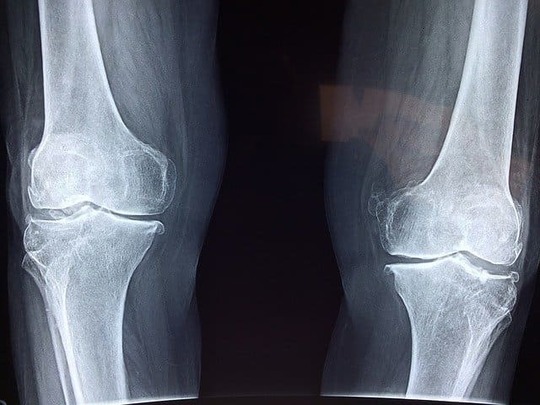

場合によっては、骨移植や血管の移植などを行うこともあります。手術が必要かどうかという判断はレントゲン写真から壊死の進んでいる度合いや、破壊の状態を見て決めます。